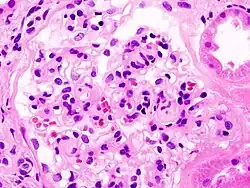

_HE.jpg)

Diabetic kidney disease (DKD) (or Diabetic nephropathy) is a progressive microalbuminuria disease with a slight loss of albumin in the urine (30–300 mg per day); DKD has been viewed as a diabetic complication-related microvascular disorder in a renal manifestation.[23] In kidney biopsy, DKD is characterized by glomerular and tubular basement thickening, mesangial expansion, glomerulosclerosis, podocyte effacement (histology) and nephron loss.[24] DKD occurs in 30%-50% of the diabetic patient population and leads to kidney failures in up to 20% of the type 1 diabetic patients.[24] However, a substantial portion of DKD patients do not manifest albuminuria.[24] DKD pathogenesis is attributed to the dysregulated glucose transport at a higher glucose level and the excessive influx of intracellular glucose into endothelial cells.[23] The elevated glucose level is sustained along with multiple metabolic phenotypes such as excess fatty acids and oxidative stress, as well as shear stresses induced by hypertension and hyperfusion, and can lead to microvascular rarefaction, hypoxia and maladaptation in glomerular neoangiogenesis.[23]